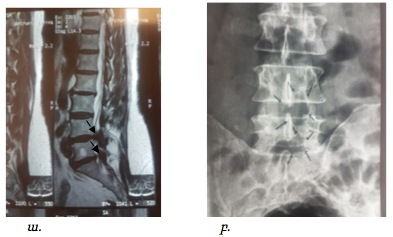

Նման վիրահատությունների արդյունավետության մասին է վկայում նկար 10-ում ներկայացված նախավիրահատական և հետվիրահատականհետազոտությունների համեմատականը:

Նկ. 10 Ողնաշարային խողովակի երկու մակարդակի նեղացումով հիվանդի նախավիրահատական և հետվիրահատական հետազոտման նկար

ա. ՄՌՏ հետազոտում համաձայն որի առկա է L4-L5 և L5-S1 մակարդակների նեղացում (ցույց է տրված սլաքով)

բ. Նույն հիվանդի հետվիրահատական ռենտգեն հետազոտում, համաձայն որի առկա են L4-L5 և L5-S1 մակարդակների ողերի աղեղների մասնակի հեռացում, ինչը համապատասխանում էր ախտահարված մակարդակներին (ցույց է տրված սլաքով)